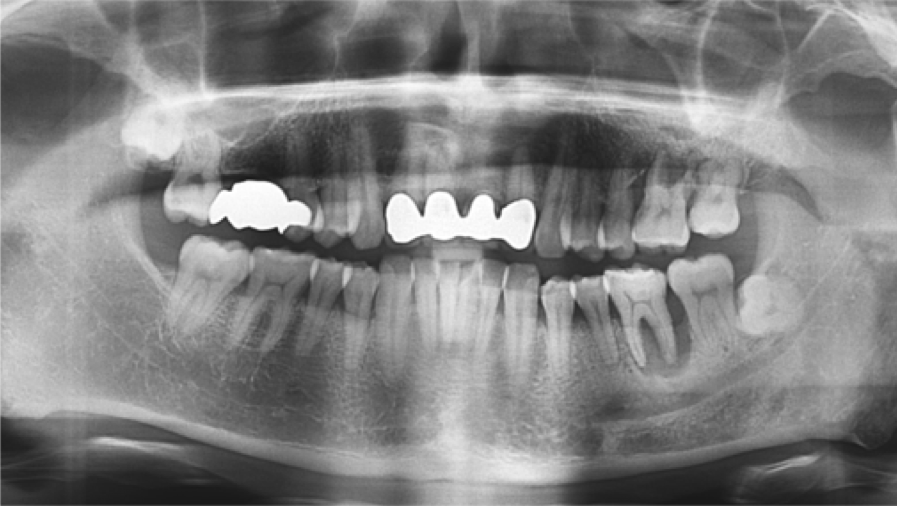

Clinical case: Bone filling into the bottom of deepest thread at 8.0mm AnyRidge fixture

- Courtesy of Dr. Kwang Bum Park -

Keywords

AnyRidge, Knifethread ,extraction socket, ,initial stability ,Allograft, ,osseointegratio ,Dr. Kwang Bum Park, , Mandibular, Single replacement, AnyRidge, Mega-oss,

Products used

Implant system-AnyRidge, Regeneration-Mega-Oss